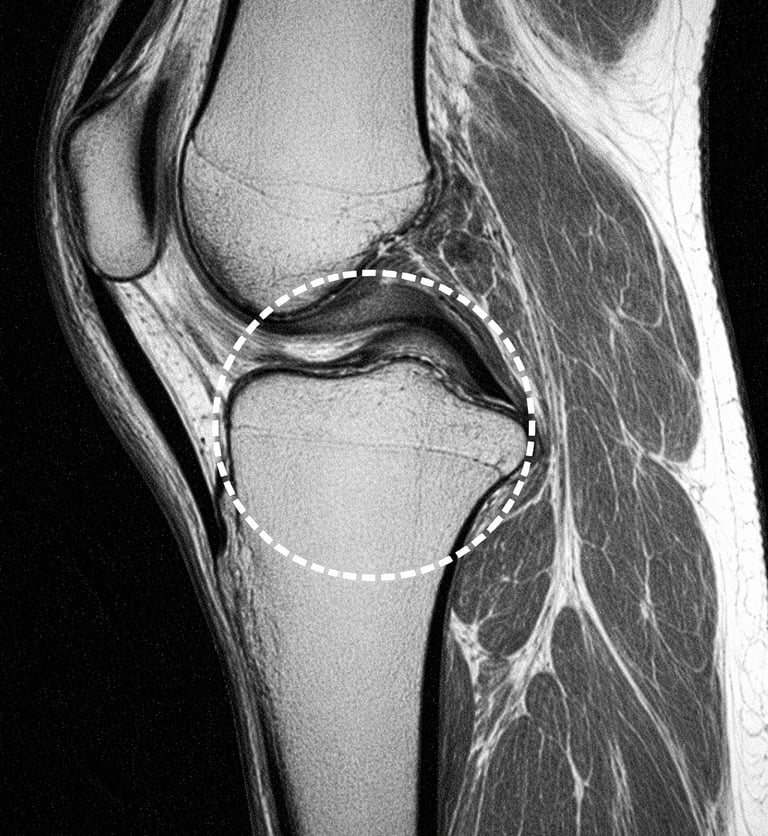

IRM du genou

Lésion du ménisque

Une lésion du ménisque peut provoquer une douleur lors de certains mouvements du genou.